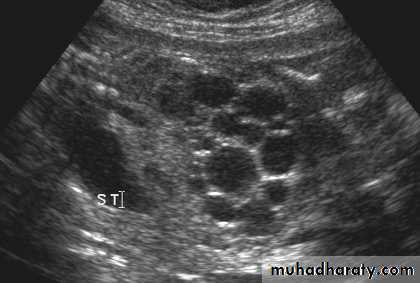

Simple (solitary) renal cyst

Common condition.Single or multiple.

Uni or bilateral.

Congenital or acquired.

Usually asymptomatic. In 10% symptomatic: pain, heaviness, infection, bleeding inside the cyst or pressure effect on the ureter causing hydronephrosis.

Examination: usually –ve, big cyst cause painless loin mass, & painful if complicated by bleeding or infectionU/S: echo free area (cystic lesion).